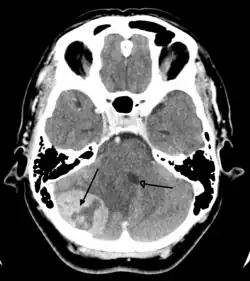

Brain tumors, when compared to tumors in other areas of the body, pose a challenge for diagnosis. Commonly, radioactive tracers are uptaken in large volumes in tumors due to the high activity of tumor cells, allowing for radioactive imaging of the tumor. However, most of the brain is separated from the blood by the blood–brain barrier (BBB), a membrane that exerts a strict control over what substances are allowed to pass into the brain. Therefore, many tracers that may reach tumors in other areas of the body easily would be unable to reach brain tumors until there was a disruption of the BBB by the tumor. Disruption of the BBB is well imaged via MRI or CT scan, and is therefore regarded as the main diagnostic indicator for malignant gliomas, meningiomas, and brain metastases.[41]

Imaging

Medical imaging plays a central role in the diagnosis of brain tumors. Early imaging methods – invasive and sometimes dangerous – such as pneumoencephalography and cerebral angiography have been replaced by non-invasive, high-resolution techniques, especially magnetic resonance imaging (MRI) and computed tomography (CT) scans.[42] MRI with contrast enhancement is the preferred imaging test in the diagnosis of brain tumors.[24][43] Glioblastomas usually enhance with contrast on T1 MRI weighted MRI imaging, and on T2 with FLAIR imaging showing hyperintense cerebral edema.[24] Low grade gliomas are usually hypointense on T1 MRI, and hyperintense with T2 with FLAIR MRI. Meningiomas are usually homogenously enhanced with dural thickening on MRI.[24]